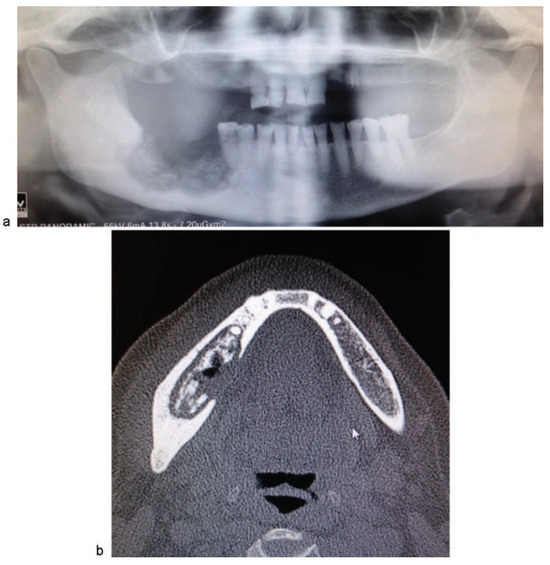

Clinical Cases